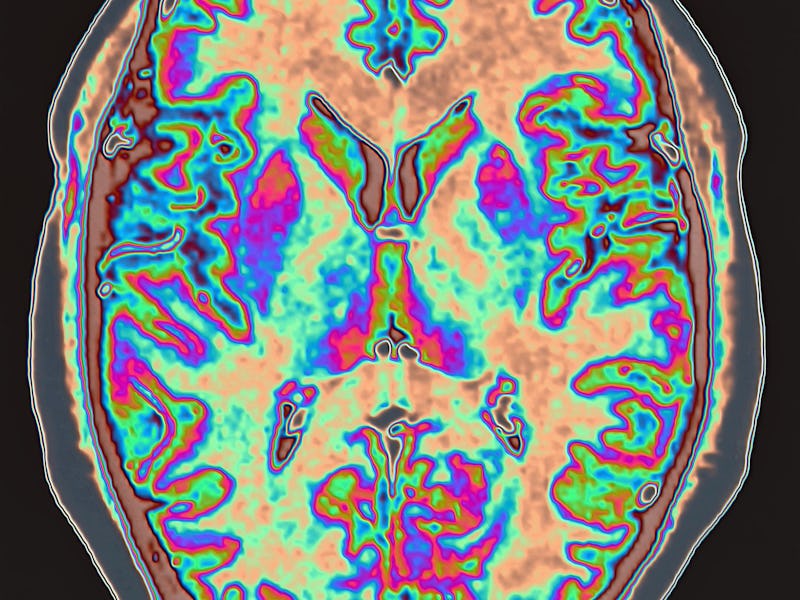

One important discovery was that concussed rugby union players have more “free radicals” – unstable, cell-damaging molecules – in their blood. They also have less nitric oxide, a beneficial molecule which allows more oxygen and glucose to get to the brain. As a result, blood vessels in the concussed brain react sluggishly to changes in blood flow, a condition known as “cerebrovascular impairment”.

Cerebrovascular impairment has been linked to cognitive dysfunction, and can have a negative effect on the way a person thinks, concentrates, formulates ideas, and remembers. It can also make them more vulnerable to dementia in later life. In our analysis, these impairments were mostly seen in the regions of the brain where head contact is most frequently made during play.